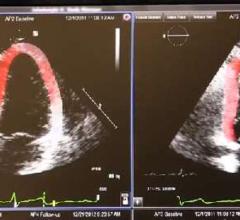

This channel includes news and new technology innovations about cardio oncology, the subspeciality of monitoring, preventing and treating cardiovascular damage caused by cancer treatments such as chemotherapy and radiation therapy. Chemo and radiation can damage or kill cardiac muscle cells, which can result in reduced cardiac pumping capacity. The speciality of cardio-oncology monitors cardiac performance with a baseline echocardiogram and followup imaging during treatments to ensure the heart is not damaged.

June 19, 2018 — Clinical practice, along with guidelines and research, have shown that speckle tracking strain imaging ...

Cardio-oncology is an emerging field that combines the expertise of both cardiology and oncology to assess and treat ...